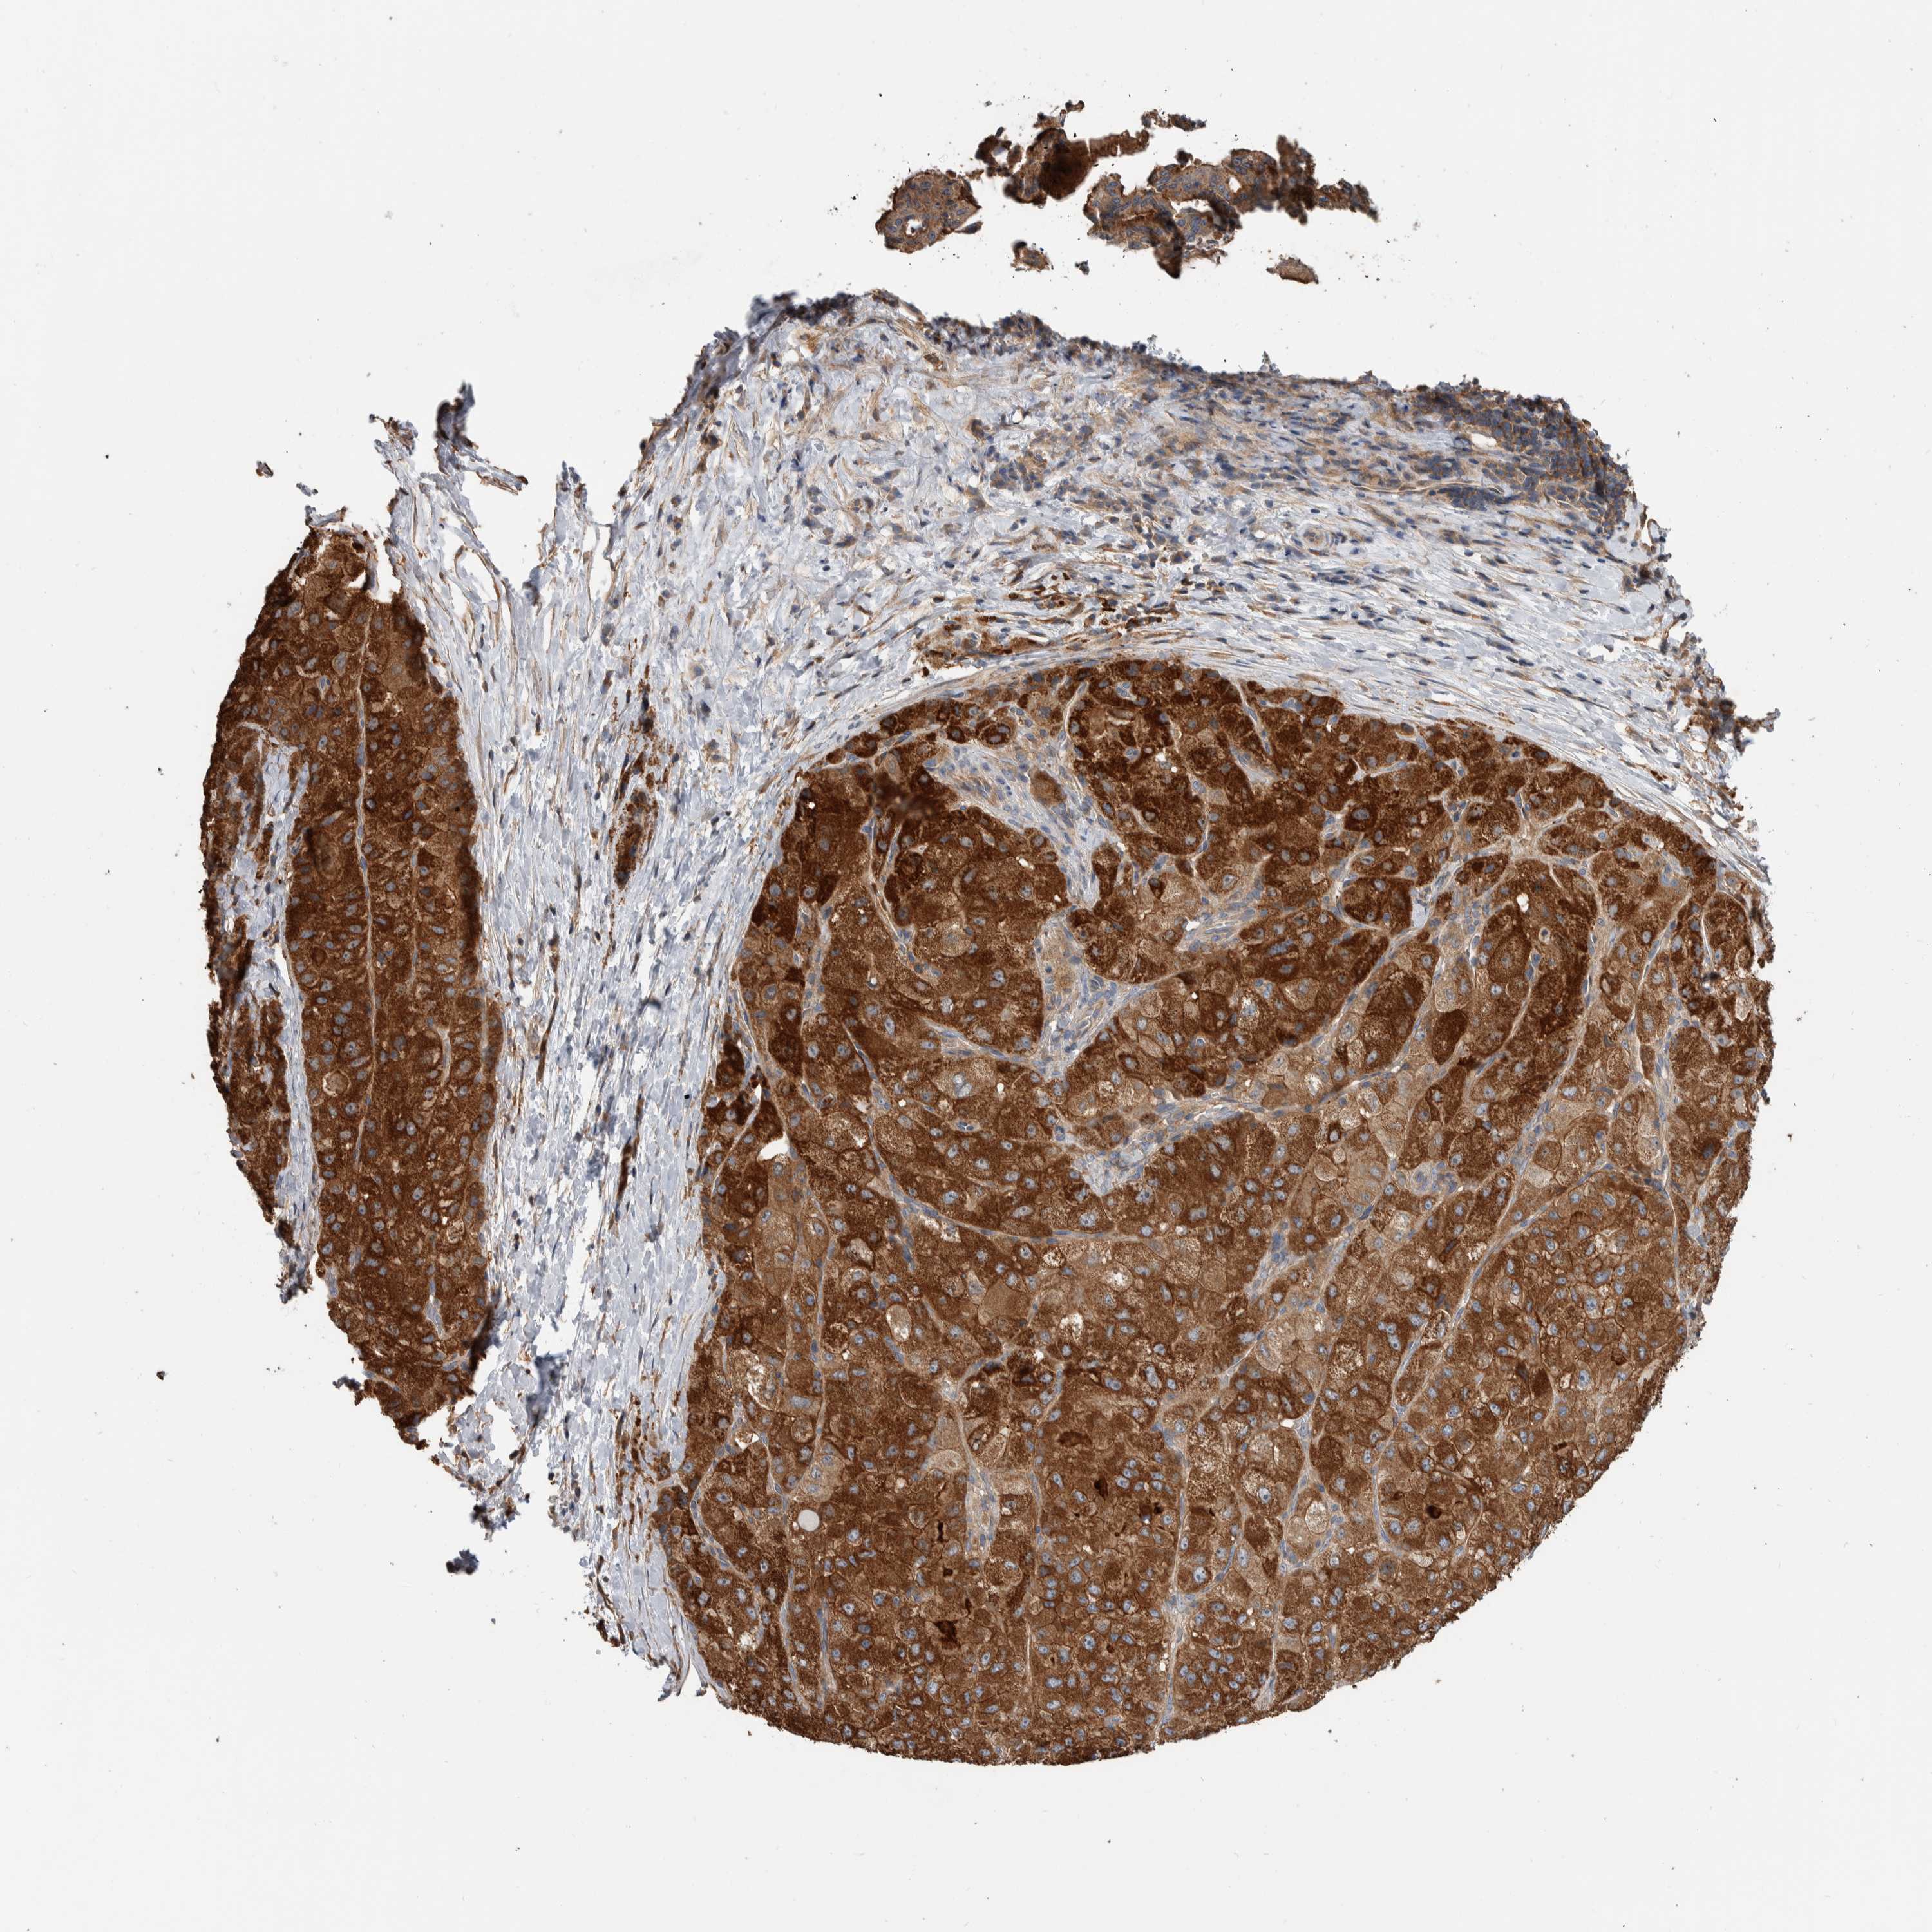

LIVER CANCER - Protein expressioni

A mouse-over function shows sample information and annotation data. Click on an image to view it in a full screen mode. Samples can be filtered based on level of antibody staining by selecting one or several of the following categories: high, medium, low and not detected. The assay and annotation is described here.

Note that samples used for immunohistochemistry by the Human Protein Atlas do not correspond to samples in the TCGA dataset.

Antibody stainingi

Antibody staining in the annotated cell types in the current human tissue is reported as not detected, low, medium, or high, based on conventional immunohistochemistry profiling in selected tissues. This score is based on the combination of the staining intensity and fraction of stained cells.

Each image is clickable and will lead to virtual microscopy that enables deeper exploration of all samples and also displays staining intensity scores, fraction scores and subcellular localization as well as patient and tissue information for each sample.

Antibody HPA023840

Antibody CAB012245

Staining

High

Medium

Low

Not detected

Intensity

Strong

Moderate

Weak

Negative

Quantity

>75%

75%-25%

<25%

None

Location

Nuclear

Cytoplasmic/membranous

Cytoplasmic/membranous,nuclear

Cholangiocarcinoma

Carcinoma, Hepatocellular, NOS